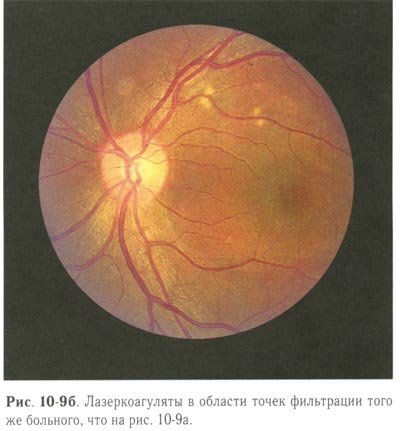

Перед лазерной коагуляцией необходимо провести ФАГД для выявления точки фильтрации и определения её локализации. Применяют 2 вида лазерной коагуляции: при наличии точки фильтрации коагуляты II степени наносятся в месте её локализации под контролем ФАГД, при отсутствии точки фильтрации производится подковообразная лазерная коагуляция по краю отслойки пигментного эпителия (рис. 10-9, 10-10; см. рис. 10-12).

Лазеркоагуляты в области точек фильтрации того же больного. |